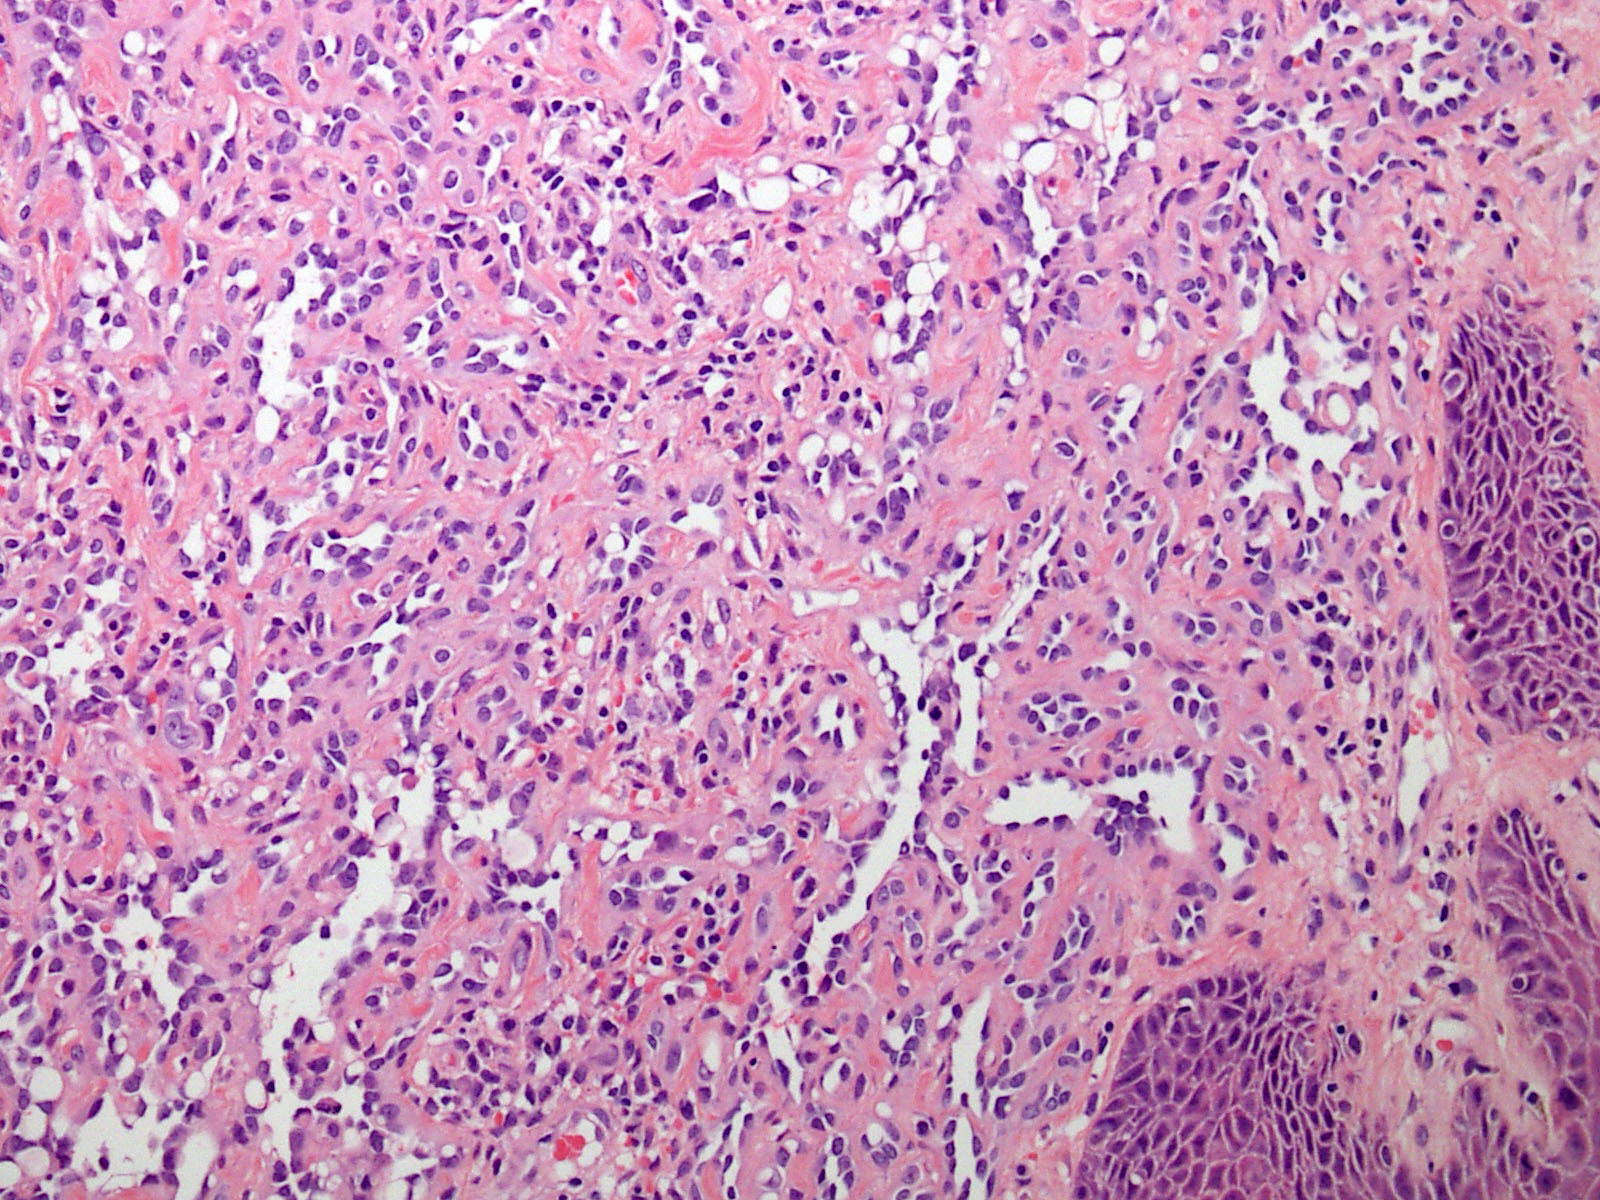

Microscopic (histologic) description

- Poorly circumscribed lesion, infiltrating dermis and subcutis with dissecting planes (Int J Clin Exp Pathol 2010;3:528)

- Endothelial cells are bland with hobnailed hyperchromatic nuclei

- Nuclear atypia is not seen

- Mitotic figures are rare

- Lesional stroma is fibrotic and shows lymphoid infiltrate (J Med Case Rep 2021;15:69, Int J Clin Exp Pathol 2010;3:528)

- Occasional solid growth may be seen (Stockman: Diagnostic Pathology - Vascular, 1st Edition, 2015)

Microscopic (histologic) images